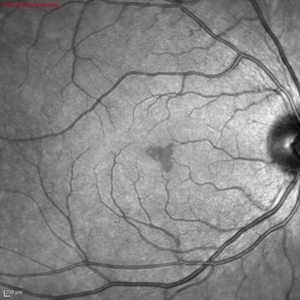

Acute Macular Neuroretinopathy

Mar 25 2024 by Daniel Davis, OCT-C

18 yo female presenting with hazy vison for 2-3 weeks. VA OD: sc20/20 VA OS: sc20/20 Infrared imaging showed dark gray, petalloid, perifoveal lesions and OCT shows focal signal reduction of the Inner Segment / Outer Segment junction. Elects to observe.

Photographer: Daniel Davis, OCT-C, The Retina Institute, St. Louis

Imaging device: Optos California SWL

Condition/keywords: acute macular neuroretinopathy